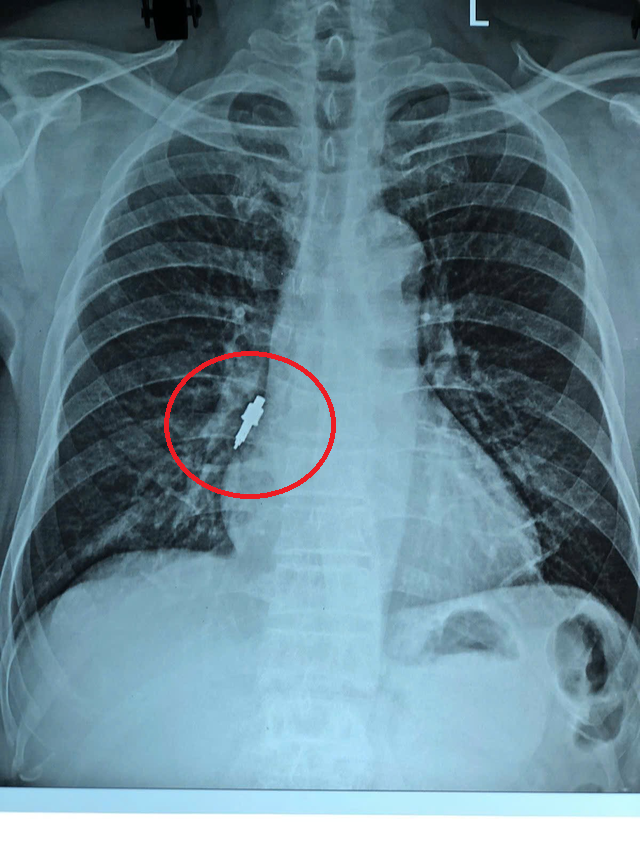

Dị vật trong phế quản của bệnh nhân. Ảnh: BVCC.

Sau đó, bệnh nhân xuất hiện ho nhẹ kéo dài. Khi cơn ho trở nên dữ dội, gia đình đưa ông đi khám. Kết quả chụp X-quang cho thấy có dị vật nằm trong phế quản phải nên bệnh nhân được chuyển gấp tới Bệnh viện Hữu Nghị.

Tại đây, các bác sĩ quyết định tiến hành nội soi phế quản cấp cứu. Dị vật được xác định bằng inox, bề mặt trơn, đường kính 1cm, dài 2,5cm và mắc sâu vào phế quản phải, kìm sinh thiết thông thường không thể gắp ra.

Dị vật như chiếc mũi khoan trong đường hô hấp của bệnh nhân được lấy ra.